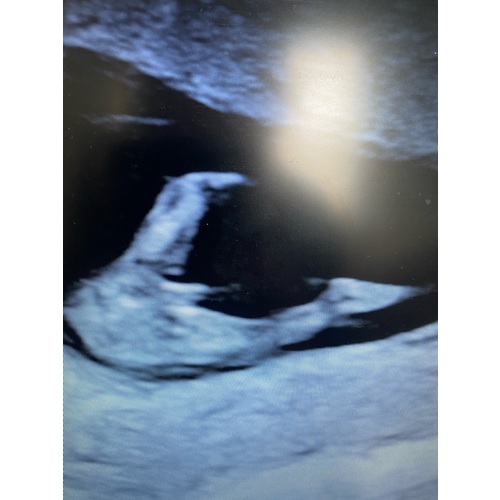

Ik denk ook niet dat dat de nub is. Misschien is er iemand die bij mijn echo mee wil kijken. Je lijkt bij mijn foto de nub te zien.

Is dat niet gewoon de navelstreng? De nub zit volgens mij veel lager

Nee die was nog niet te zien volgens de VK...

Zie het bij jou dus niet....